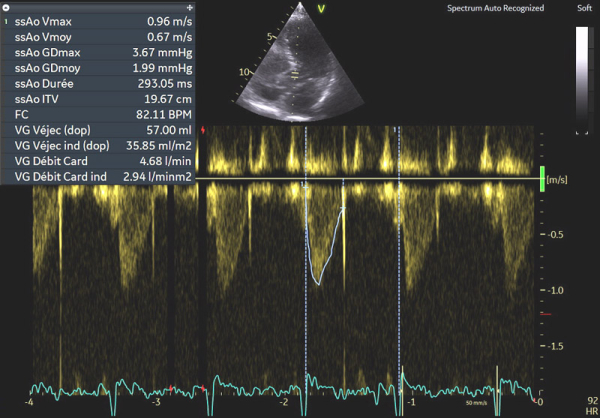

Image 6 : échocardiographie Doppler pulsé sous aortique avec estimation du débit cardiaque

En cas d’atteinte précoce d’amylose cardiaque, ce sont en effet les premières anomalies à pouvoir être objectivées et il peut ne pas y avoir encore d’altération marquée du SLG (cf Image 7), de signe de dysfonction diastolique VG (cf Images 3 et 4), de dilatation de l’OG (cf Image 8), de dysfonction systolique du VD (cf Image 5) et les pressions peuvent être normales.